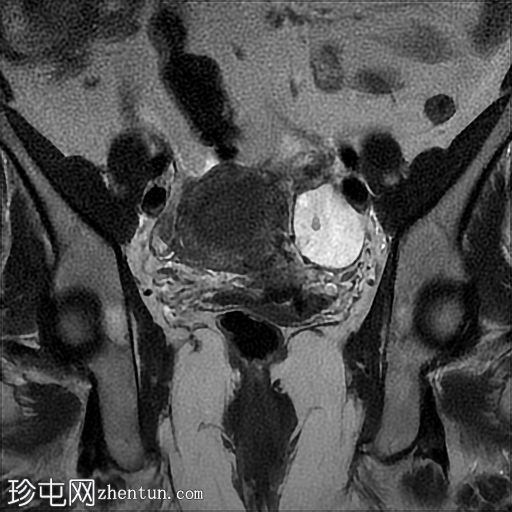

冠状位

T2加权像

3.jpg

左侧卵巢增大,呈弥漫性低T1信号和高T2信号,可见周边卵泡,部分卵泡除周边卵泡周围有环状强化外,无明显实质强化。左侧附件蒂呈漩涡状,提示卵巢扭转。